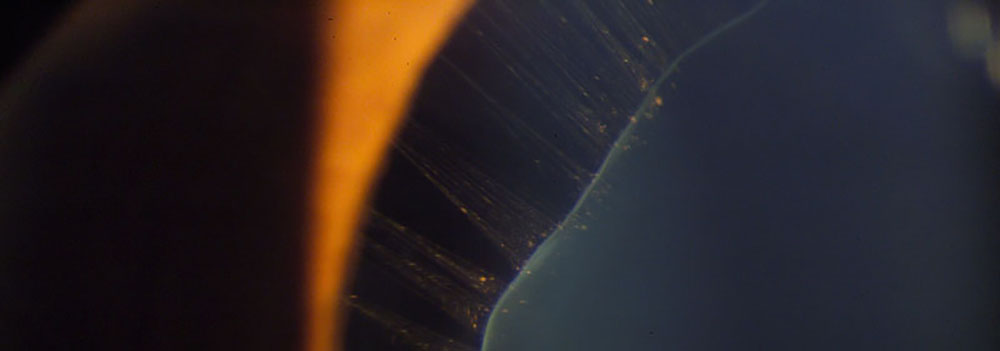

Luxación del Cristalino en Sindrome de Marfan. Fotografía, Instituto Barraquer de América